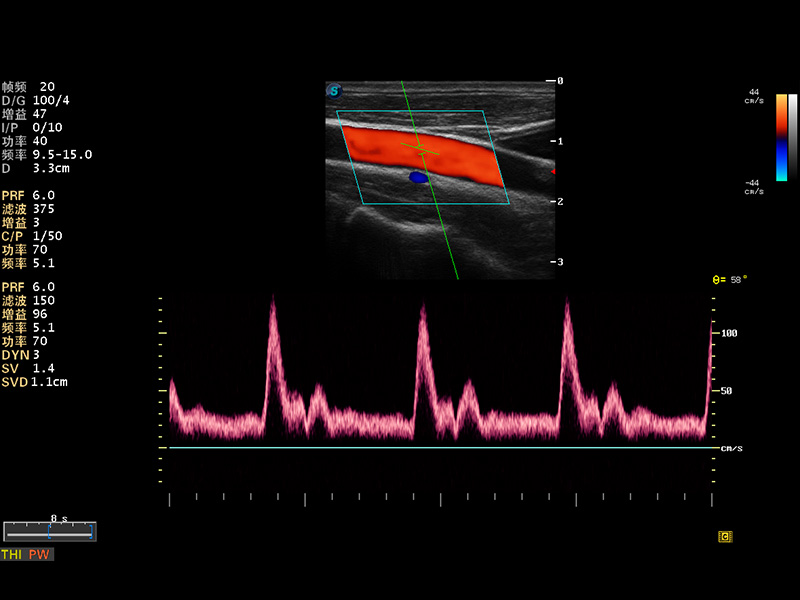

S8 EXP便携式彩色多普勒超声诊断仪是新葡的京集团8814检测站研发的高端全身应用型便携彩超。高通道的VIS平台融合可视化(Visual)、智能化(Intelligent)和人性化(Smart)的特点,配以新葡的京集团8814检测站自主研发生产的探头大家族,使您能够快速、准确的获得病人信息,提高工作效率的同时减轻疲劳。

多波束形成器